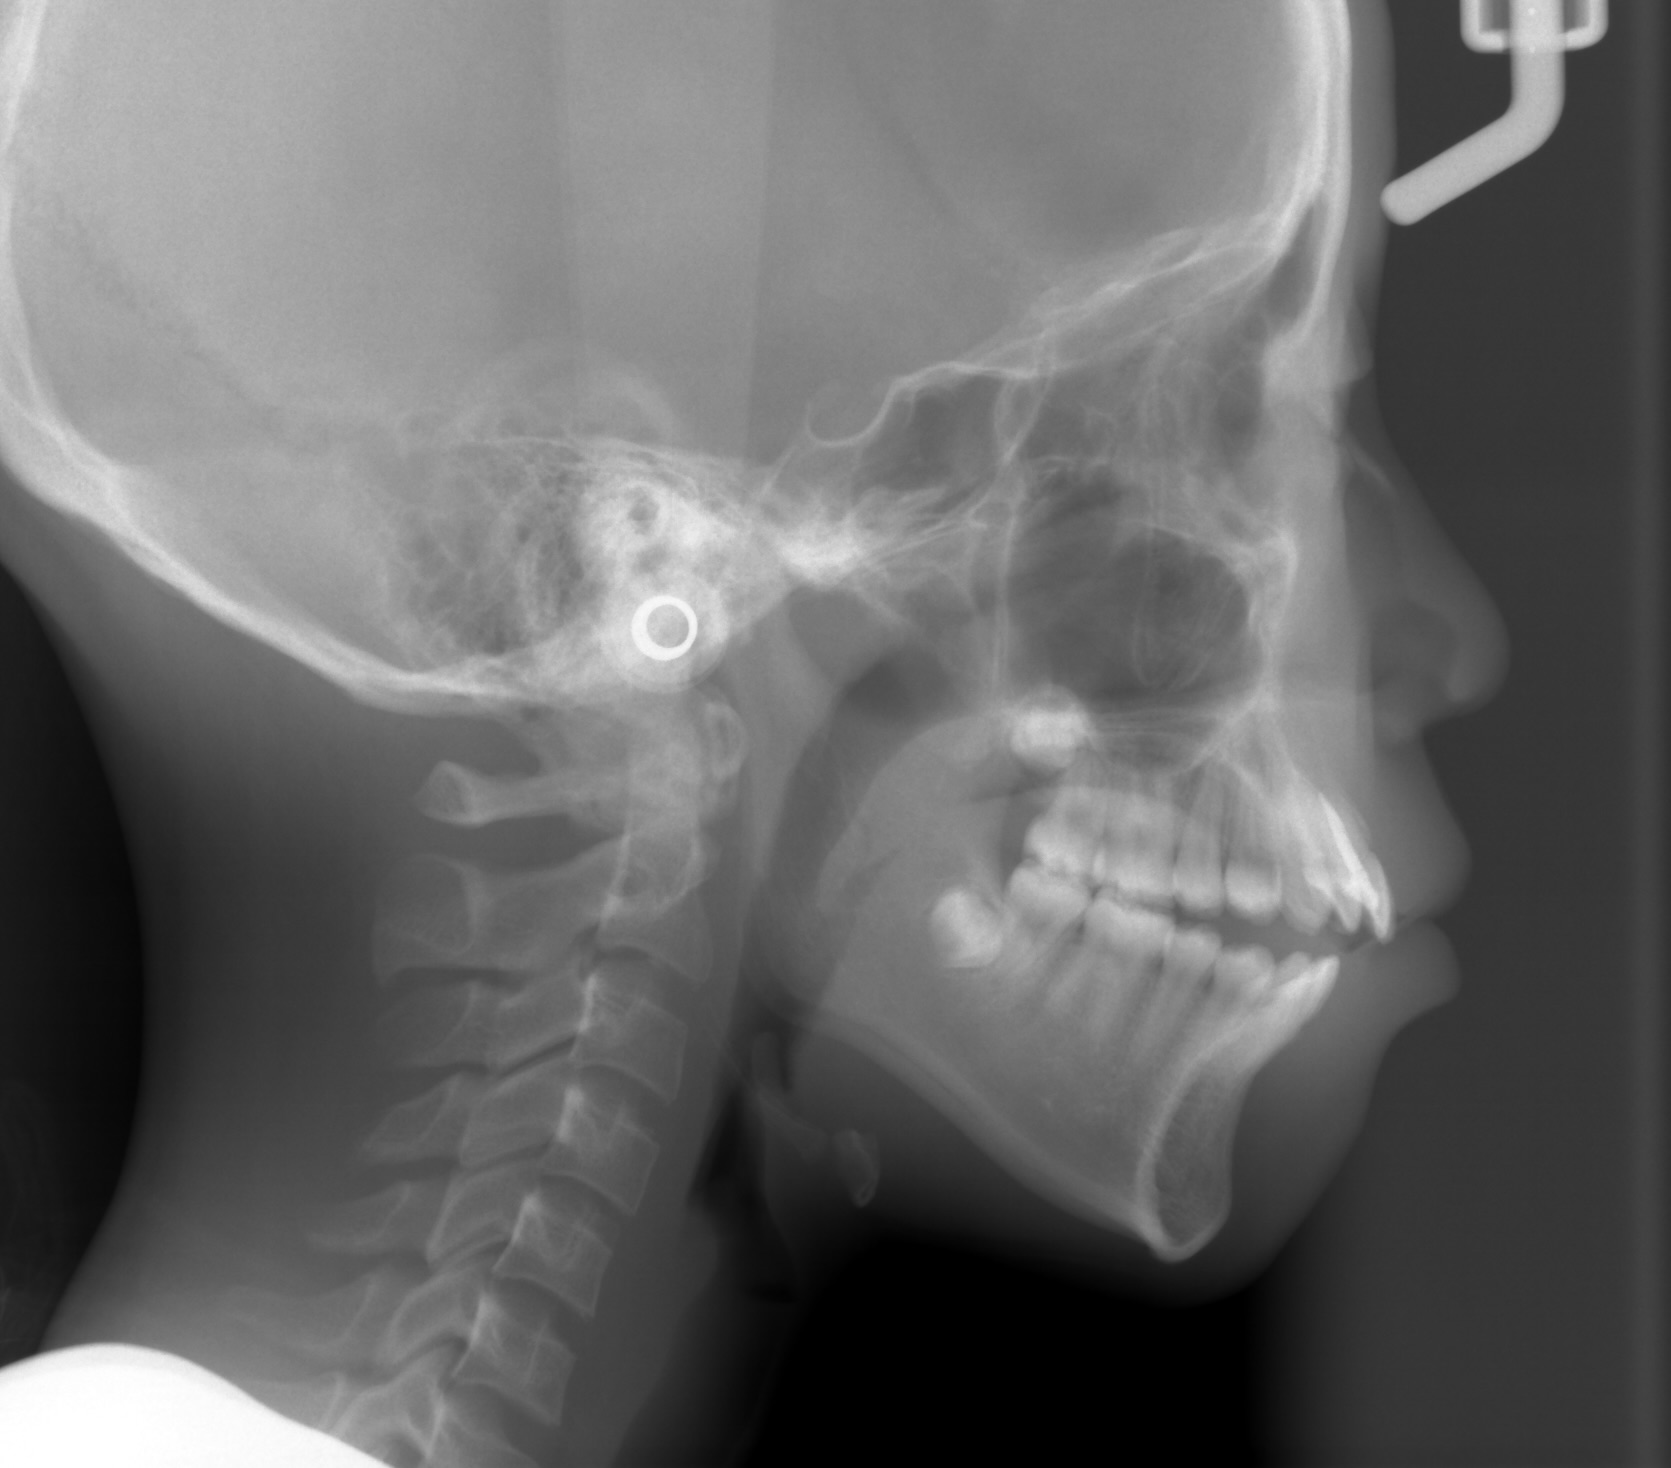

セファロレントゲンにより親知らずの存在を確認するも13歳でありすぐに抜歯することは不可能と判断。

親知らずに押され臼歯部での噛み合わせが高くなってしまい、前歯が噛まなくなってしまっている。

親知らずを抜歯してそのスペースを利用して臼歯部を圧下しつつ、前歯の噛み合わせを近づけていく。